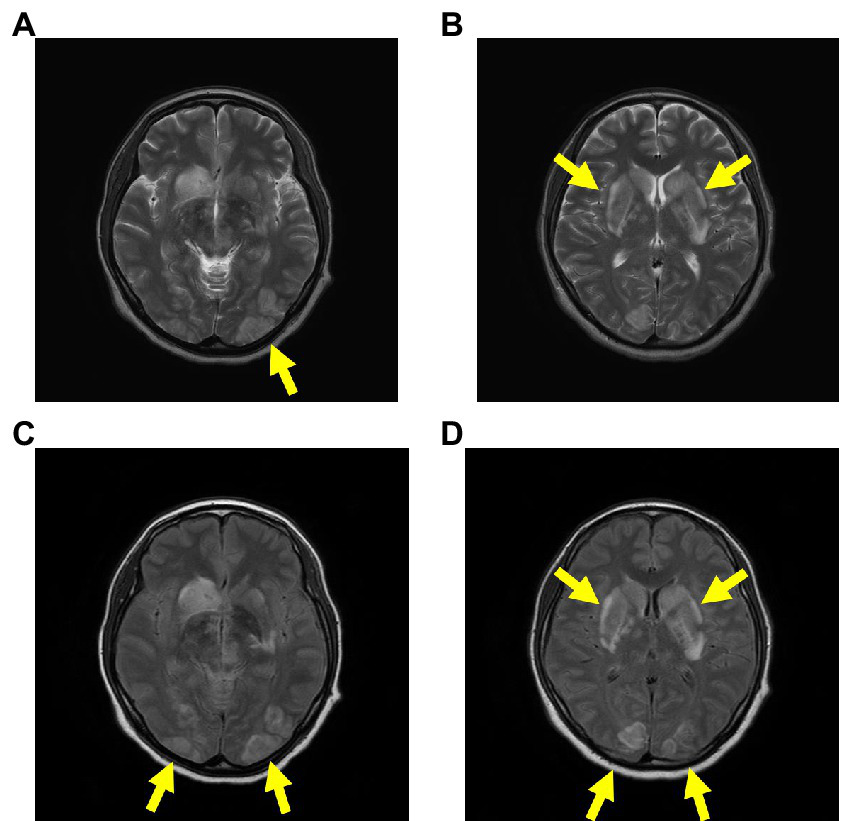

The patient was immediately intubated in the emergency department and delivered a newborn through cesarean section (CS) in the operating room. Additionally, head magnetic resonance imaging (MRI) showed a caudate nucleus hemorrhage and posterior reversible encephalopathy syndrome with hyperintense signals on T2 and fluid-attenuated inversion recovery (FLAIR) sequences in the bilateral occipital regions, caudate nucleus, and putamen (Figure 2). In this case, autoimmune antibodies measuring, ADAMTS13 activity measuring, blood smear, and liver biopsy were not performed.

Figure 2

Head MRI on admission. The head MRI reveals caudate nucleus hemorrhage and PRES, with hyperintense signals on T2 (A,B) and FLAIR (C,D) sequences in the bilateral occipital regions, caudate nucleus, and putamen. Abbreviations: MRI, magnetic resonance imaging; PRES, posterior reversible encephalopathy syndrome; FLAIR, fluid-attenuated inversion recovery.